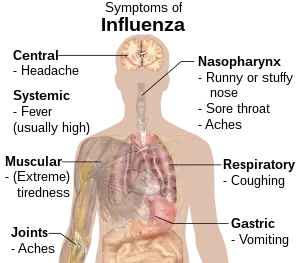

| Symptoms | Fever, runny nose, sore throat, muscle and joint pain, headache, coughing, feeling tired[1] |

blk:တုတ်ကွေးရောႏဂါႏ Influenza, commonly known as "the flu", is an infectious disease caused by an influenza virus.[1] Symptoms can be mild to severe.[5] The most common symptoms include: high fever, runny nose, sore throat, muscle and joint pain, headache, coughing, and feeling tired.[1] These symptoms typically begin two days after exposure to the virus and most last less than a week.[1] The cough, however, may last for more than two weeks.[1] In children, there may be diarrhea and vomiting, but these are not common in adults.[6] Diarrhea and vomiting occur more commonly in gastroenteritis, which is an unrelated disease and sometimes inaccurately referred to as "stomach flu" or the "24-hour flu".[6] Complications of influenza may include viral pneumonia, secondary bacterial pneumonia, sinus infections, and worsening of previous health problems such as asthma or heart failure.[2][5]

The time between exposure to the virus and development of symptoms, called the incubation period, is 1–4 days, most commonly 1–2 days. Many infections, however, are asymptomatic.[23] The onset of symptoms is sudden, and initial symptoms are predominately non-specific, including fever, chills, headaches, muscle pain or aching, a feeling of discomfort, loss of appetite, lack of energy/fatigue, and confusion. These symptoms are usually accompanied by respiratory symptoms such as a dry cough, sore or dry throat, hoarse voice, and a stuffy or runny nose. Coughing is the most common symptom.[24] Gastrointestinal symptoms may also occur, including nausea, vomiting, diarrhea,[25] and gastroenteritis,[26] especially in children. The standard influenza symptoms typically last for 2–8 days.[27] A 2021 study suggests influenza can cause long lasting symptoms in a similar way to long COVID.[28]